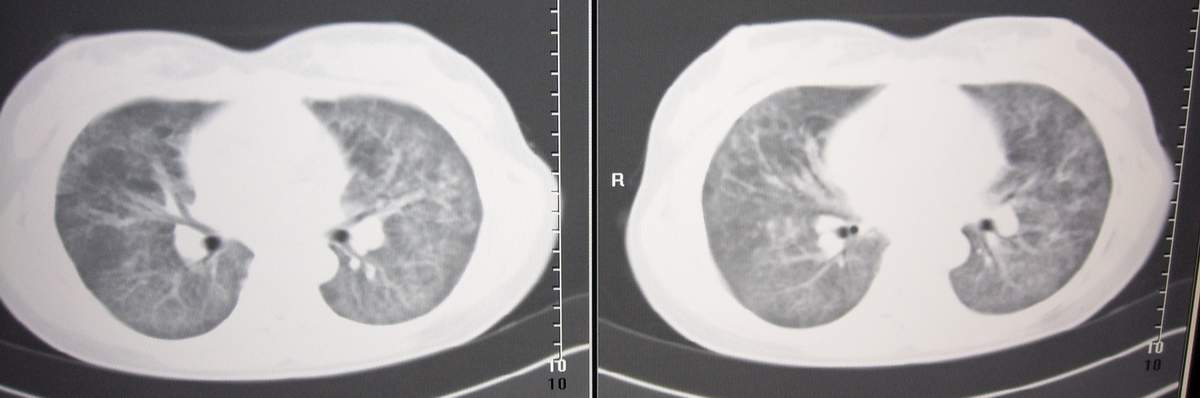

女,咳嗽、气喘2月余。

双肺纹理增多,紊乱,呈网格状,期间搀杂斑片及磨玻璃样阴影.考虑;感染性病变_首先考虑:特殊感染:嗜酸性肺病.

双肺弥漫性病变, 冠状重建肺血管增粗,建议继续上传详细临床资料,x线片

双肺弥漫磨玻璃样影,边界不清,似蝶翼征。肺纹理增多。

考虑:肺泡蛋白沉积症。建议临床进一步检查。